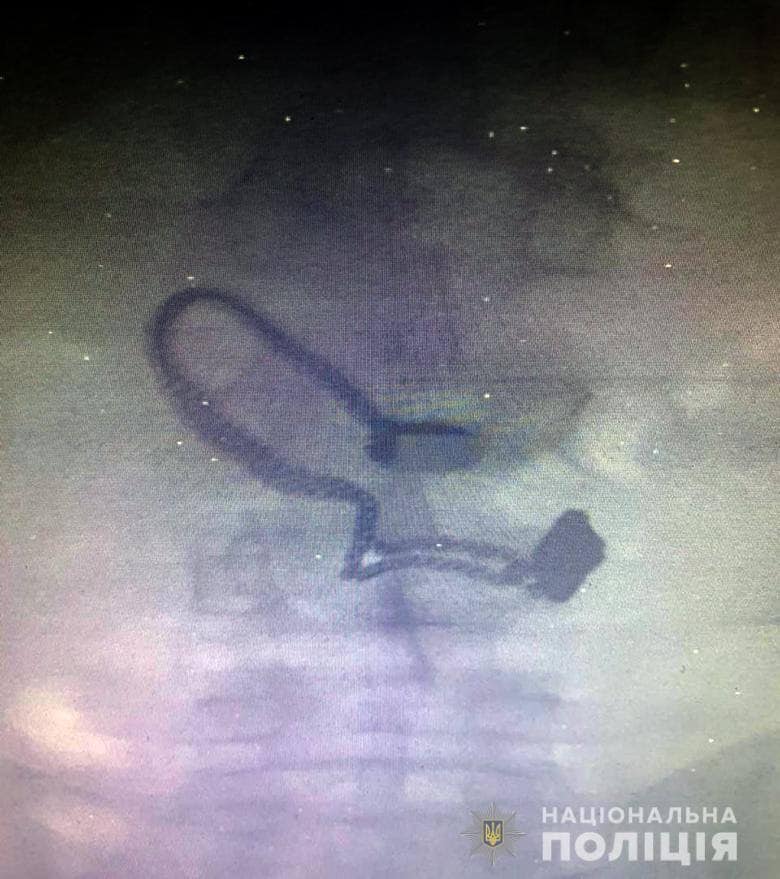

"Злоумышленника остановили неравнодушные граждане, которые стали свидетелями преступления. Это - 26-летний житель Луганской области, ранее судимый за кражи. Его задержали в порядке статьи 208 Уголовно-процессуального кодекса Украины". Во время поверхностного осмотра у мужчины нашли кошелек потерпевшей. Впоследствии он признался полицейским, что сорвал цепочку ... и проглотил. Во время медосмотра на рентген-снимке задержанного врачи обнаружили украшение", - рассказали в полиции.

Дайте ему слабительного: в сети обсуждают вора, проглотившего цепочку потерпевшейИллюстрация к посту (facebook.com/KyivOperativ)